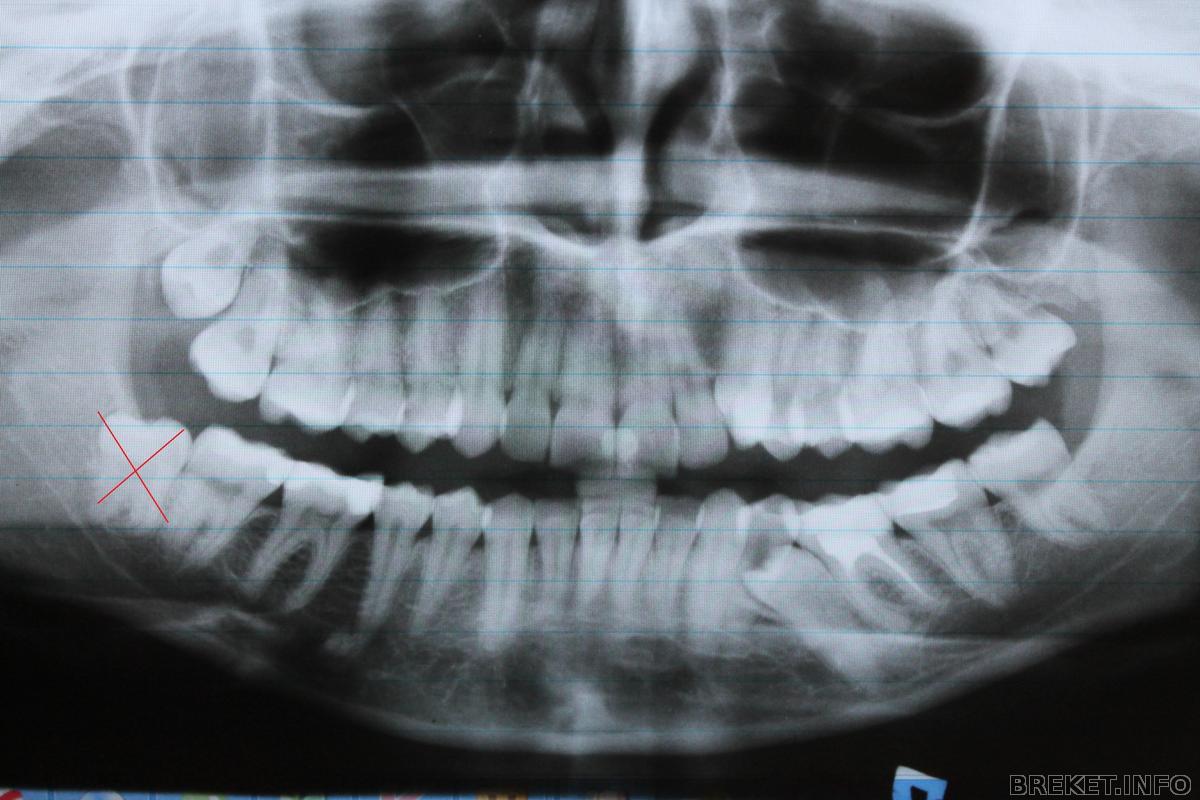

Мне 25 ( совсем не мало ). Решилась я на установку БС только после того как заболел у меня 8 зуб( мудрости), который вырос 3 года назад в десне, и торчал наполовину.

udalenie_1.jpg

Мне его удалили, резали десну, распиливали и прочие ужасы послеоперационного периода. Удалили 19.09.2013 г. лунка болит и сейчас. Челюсть так и сводит (

Далее... По совету своего стоматолога-терапевта записалась в другую клинику , по словам терапевта самом хорошему в нашем городе ортодонту, о чем не жалею. Читать далее »